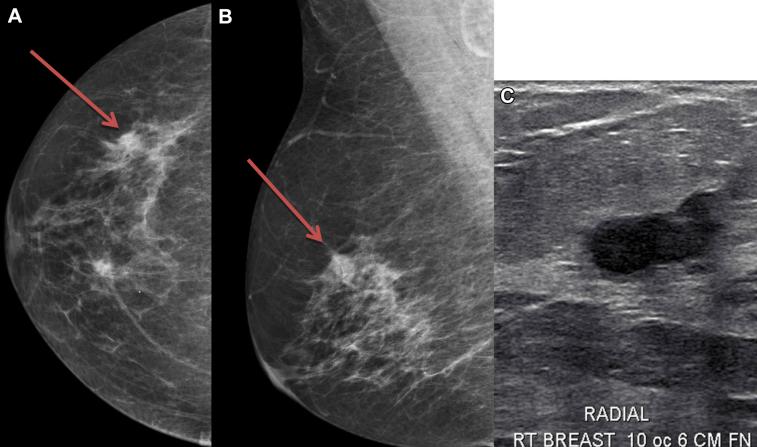

Pure primary squamous cell carcinoma of the breast (SCCB) represents around 0.1% of breast carcinomas. Diagnosis requires independence from adjacent skin without metastatic disease. SCCB is often large at presentation with nonspecific mammographic and ultrasound findings. It is typically hormone receptor negative and aggressive. Mastectomy and adjuvant chemotherapy is the most common treatment, although treatment guidelines are not well established. We present a case of pure primary SCCB detected by high risk screening mammogram and treated with breast conserving surgery, chemotherapy, and radiation. We discuss clinical, radiologic, and pathologic findings.

乳腺原发性纯鳞状细胞癌(SCCB)约占乳腺癌的0.1%。诊断需要排除邻近皮肤受累且无转移性疾病。SCCB通常在初诊时体积较大,乳房X线摄影和超声检查结果不具特异性。其通常为激素受体阴性且侵袭性强。乳房切除术和辅助化疗是最常见的治疗方法,不过治疗指南尚未完善。我们报告一例通过高危筛查乳房X线摄影发现的原发性纯SCCB病例,该病例接受了保乳手术、化疗和放疗。我们讨论了临床、放射学和病理学检查结果。